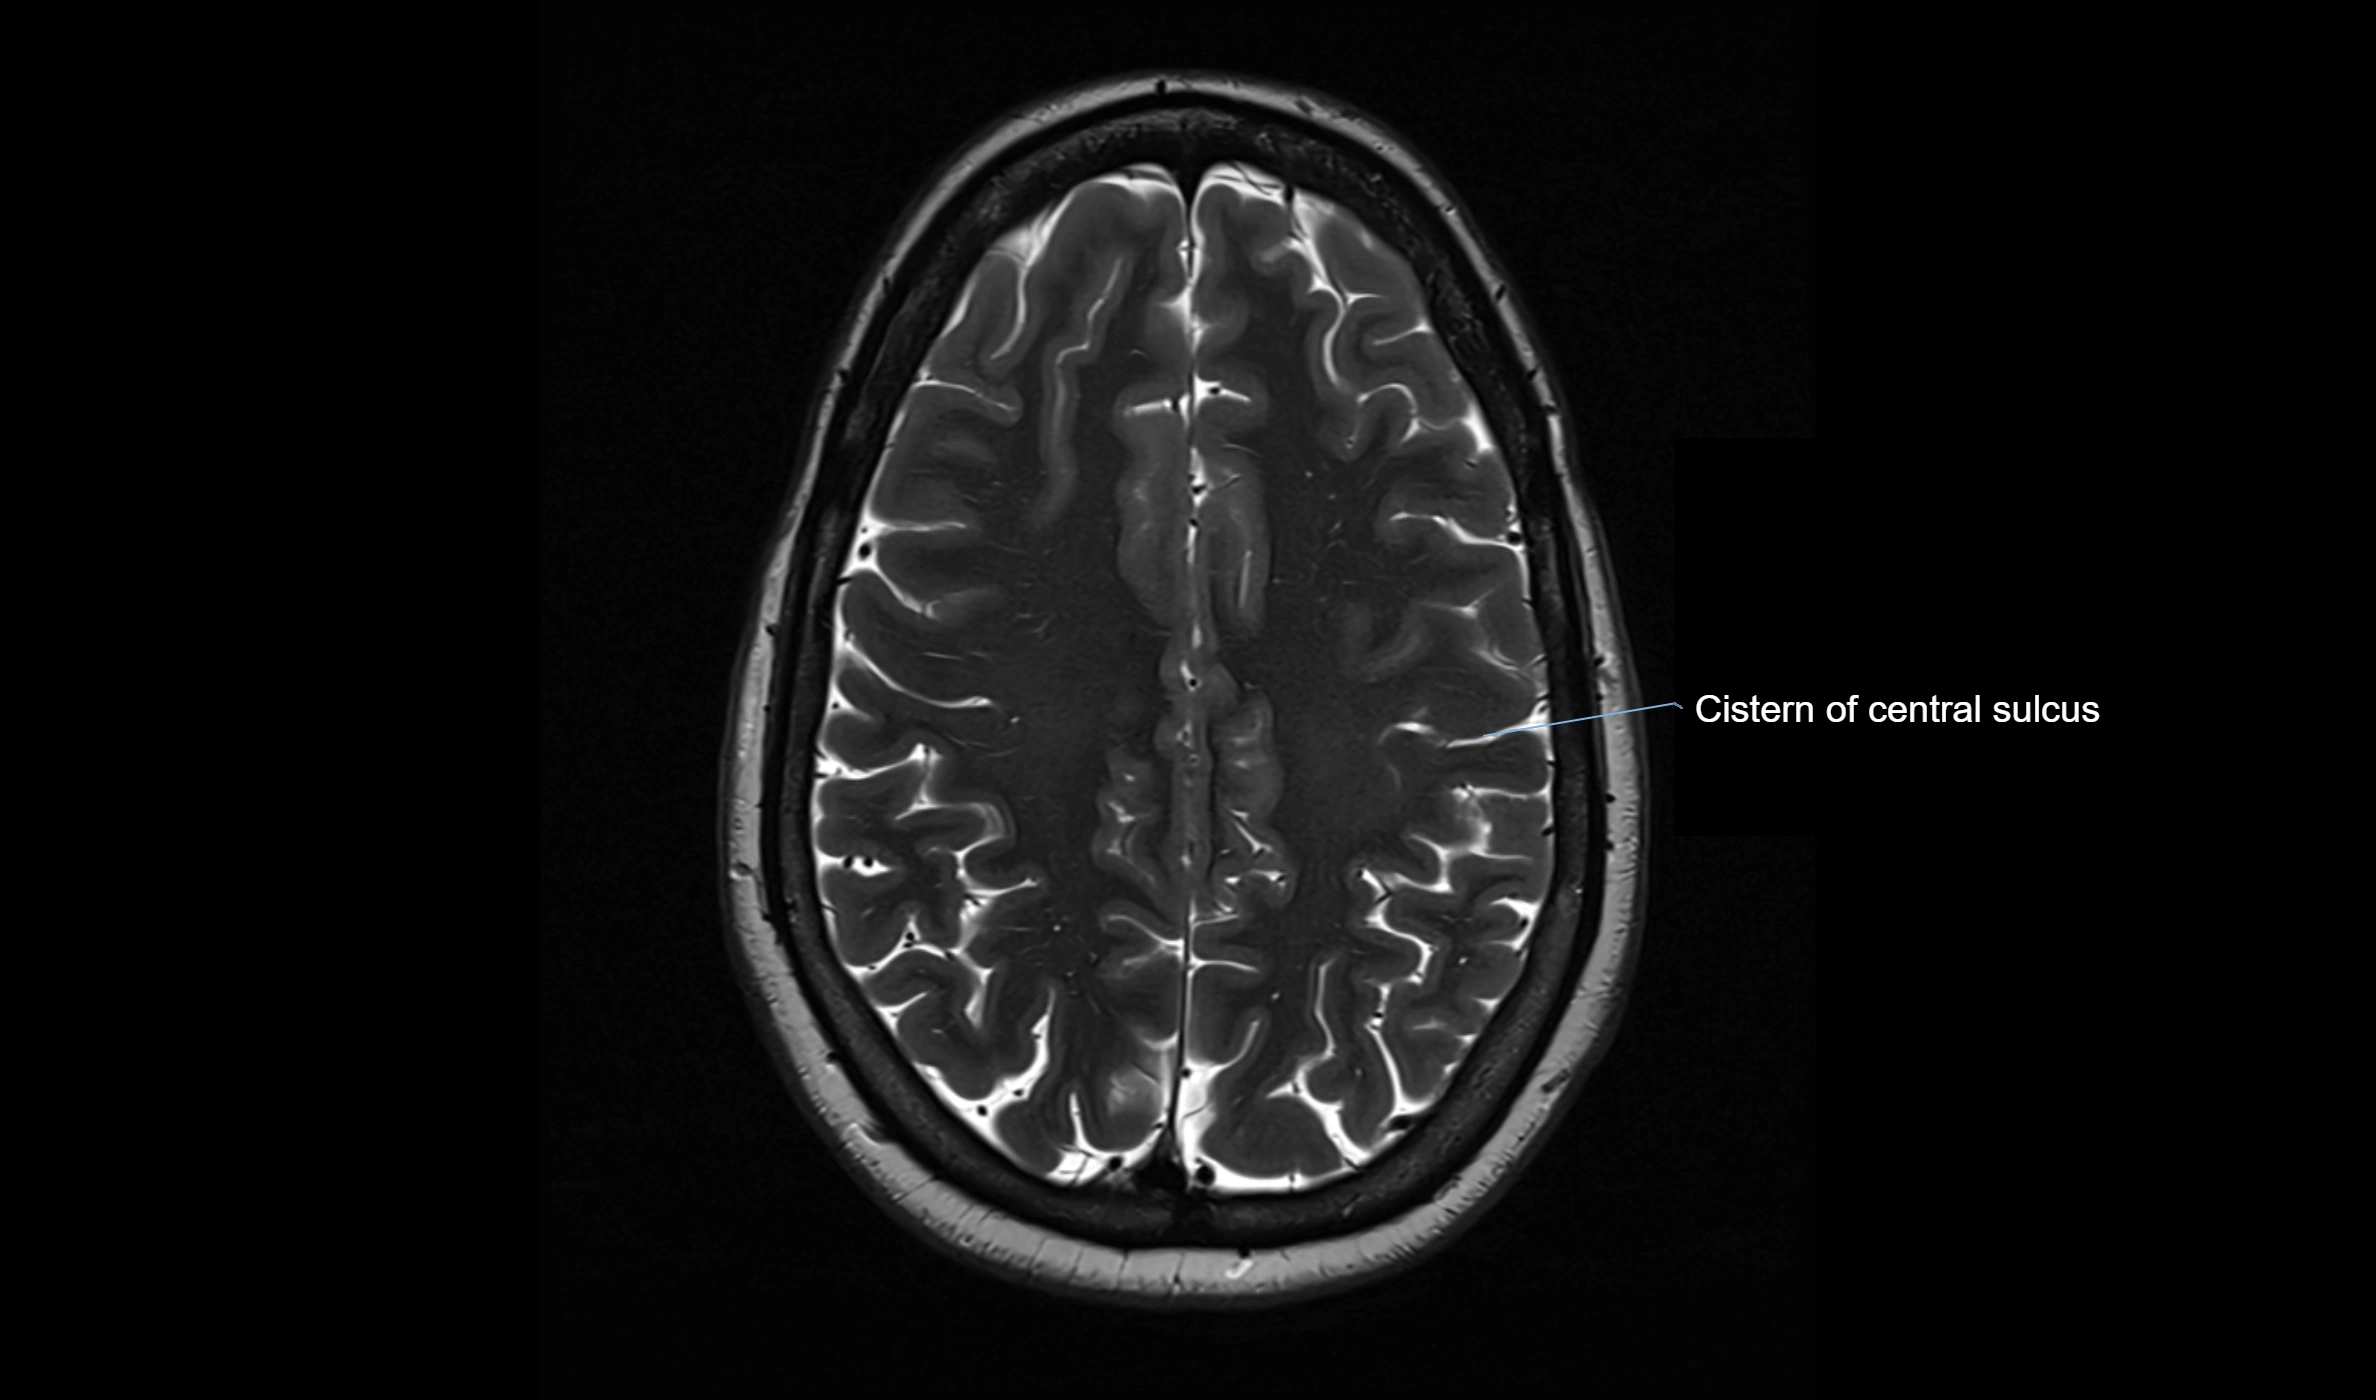

MRI images

image